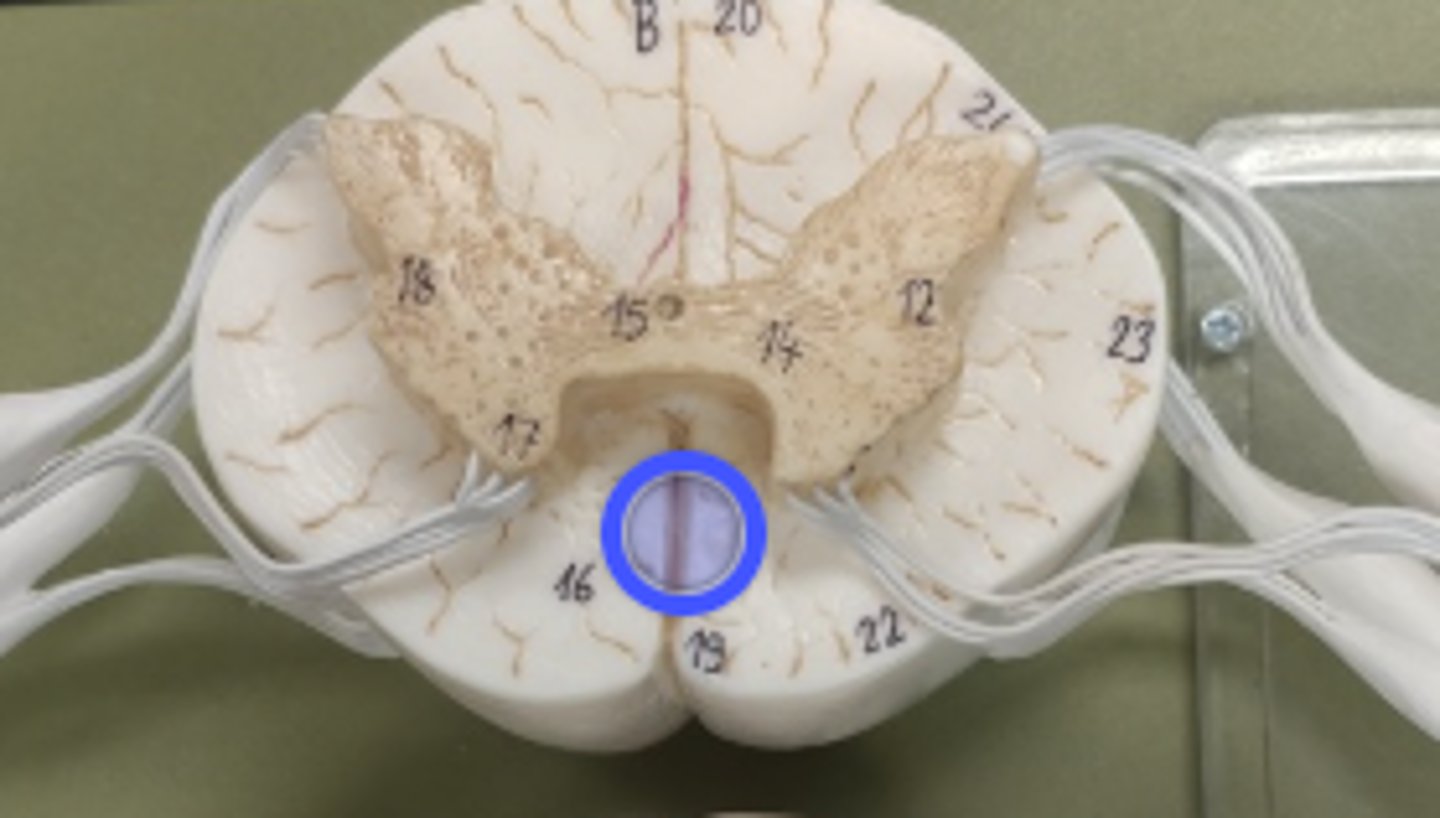

what is the blue circle surrounding?

What is number 50 or the blue dot?